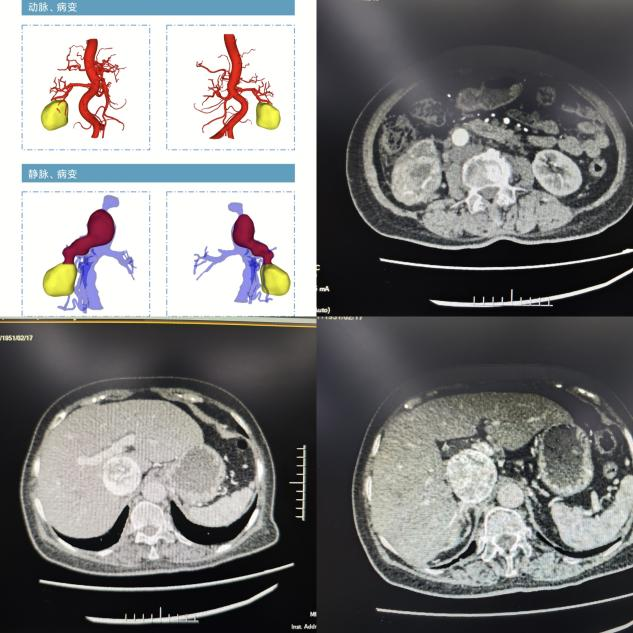

患者术前影像学检查

该患者5月前因血尿至当地医院就诊,完善B超检查发现右肾占位性病变,直径约6cm,当时未予特殊处理。1月前至当地医院复诊,MRI检查提示:右肾下极囊实性占位性病变,肿瘤沿肾门及右肾静脉向上蔓延生长,达下腔静脉旁,下腔静脉肝段受压变窄,与肿瘤分界欠清,肿瘤大小为5.8*5.3*18cm。当地医院联系昆医大附二院泌尿外科知名专家丁明霞副院长寻求帮助,丁明霞副院长了解病情后将该患者收治到医院泌尿外科一病区肾肿瘤亚专业组。随后,为全面准确地评估患者病情,由詹辉教授带领的肾肿瘤亚专业组邀请了麻醉手术科欧阳杰、肝胆胰外科田大广、放射科郭立、心脏血管外科段玉印等专家开展多学科会诊。经过讨论,专家认为该患者肿瘤增长迅速,性质倾向恶性,考虑肾透明细胞癌可能,建议行手术治疗。且相较于既往的肾恶性肿瘤切除术而言,该患者肿瘤与下腔静脉、双肾静脉关系密切,结合术前影像学分析,瘤栓已接近肝静脉平面,手术取栓难度极大、出血风险极高。

术中,见肿瘤位于患者右侧肾脏,整体呈类圆形状,大小约6*6*5cm。肿瘤与下腔静脉关系密切,侵及右肾静脉及下腔静脉,瘤栓上极超过肝短静脉水平。在充分剥离肿瘤及血管的基础上,切除上至肝短静脉上缘下达双肾静脉以下约1cm的下腔静脉、右肾静脉,并夹闭左肾静脉,将瘤栓完整取出。